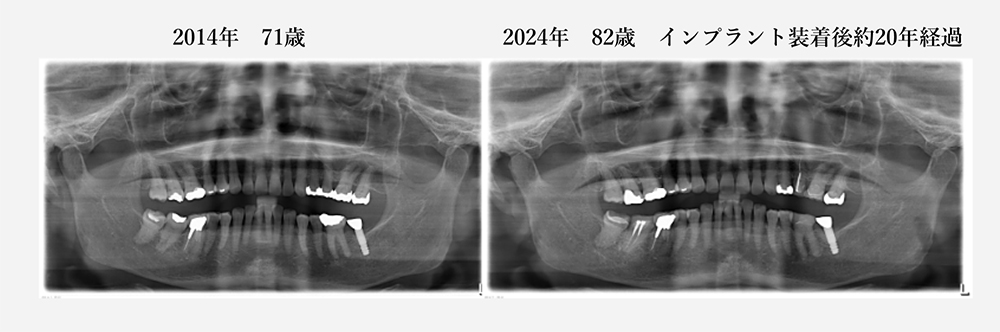

当院で20年以上メインテナンスをしていて、歯を抜くこともなく、

80歳を過ぎてもご自分の歯で美味しく食事ができています。

(デジタルレントゲン導入(2011年)後のレントゲン写真のみとなります)

現在82歳の女性